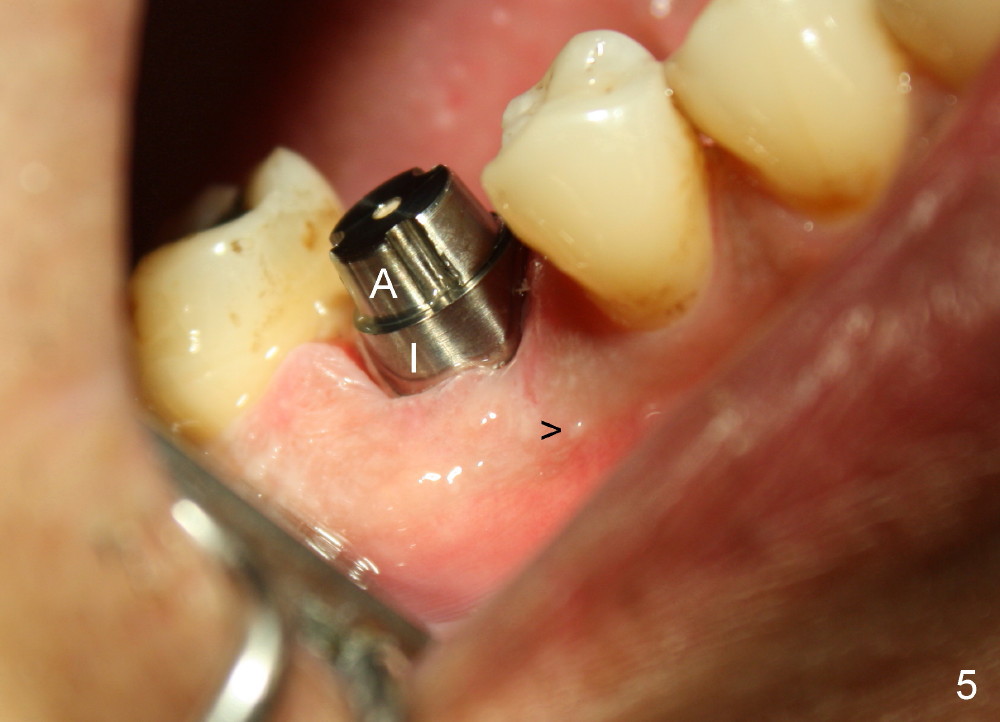

Three weeks postop, the gingiva is healthy around the implant (Fig.5 I). There is no symptom or sign of the infection (>, as compared to Fig.1). The abutment has accomplished its transient function (A, the perio dressing having dislodged) and is subsequently removed (Fig.6, to reduce micromovement of the implant and cheek and tongue bite). The 7 mm implant (I) does not look too big in its new home (alveolus). Four months postop, the mesial socket appears to have normal bony trabecular patterns (Fig.7, as compared to Fig.3).